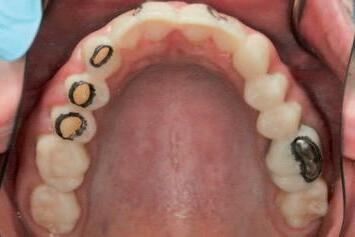

n Before initiating tooth preparation with diamond burs under copious water coolant, highly visible contrasting marks should be applied to the window perimeter of the preparation guide adjacent to the identified areas of

interference (Figure 3). These visual cues enhance intra-operative visibility and reduce the risk of over-preparation, which can occur when the guide’s reference contours are obscured by the coolant spray.

FIGURE 3: Pre-operative marking of the preparation guide with a visually contrasting colour prior to tooth reduction.

A C B